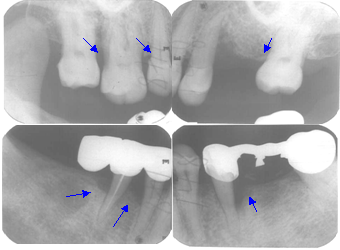

• X片示:25远中牙槽骨角形吸收至根尖,35-37远中牙槽骨角形吸收至根尖1/3区,45-44邻面牙槽骨角形吸收至根中1/2,17-16远中邻面牙槽骨水平吸收至根中1/2,上前牙牙槽骨水平吸收至颈1/3-中1/2

本例为前牙区药物性牙龈增生伴后牙区重度牙周炎,经过牙周基础治疗和两次间隔期在2-4个月的维护治疗后,前牙15×10mm的牙龈增生肿胀消失痊愈;全口4-8mm的牙周袋均减少至3-4mm以内;后牙区多个位点的角形骨吸收得到显著再生恢复;结合患者有效的自我菌斑控制,远期疗效佳。

基础治疗一年后根尖片